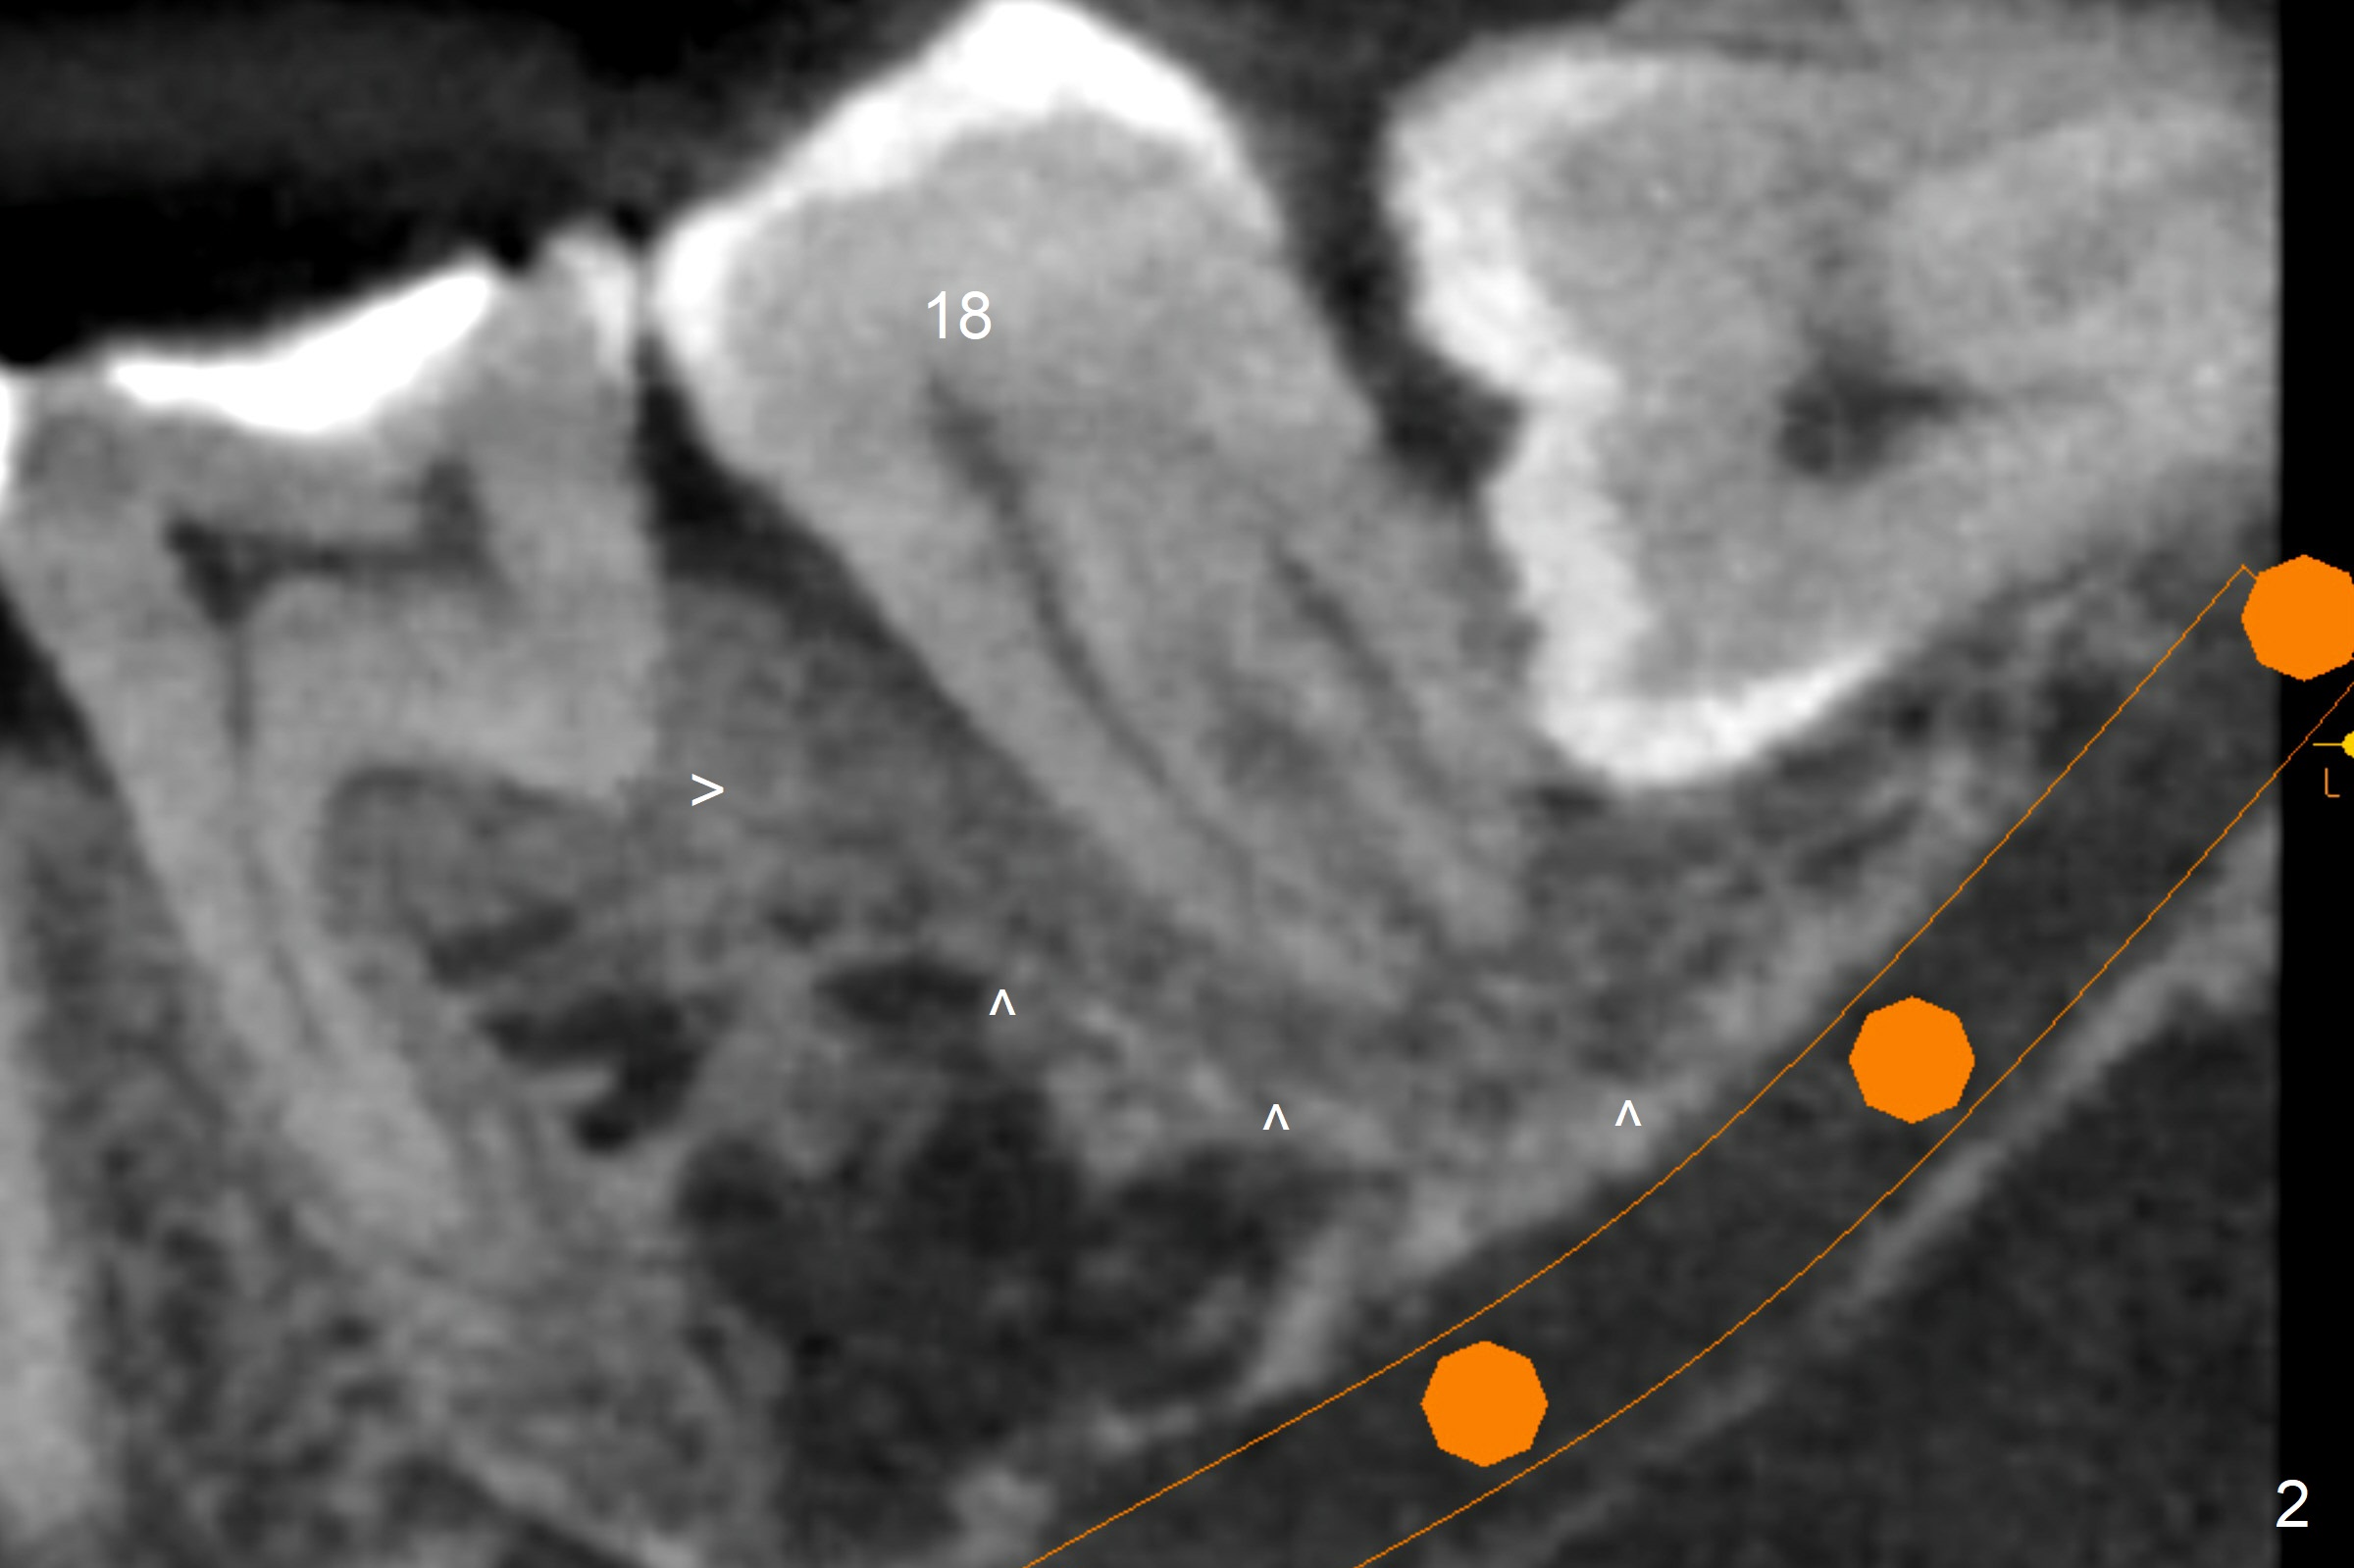

A 40-year-old man removes food debris from the lower left area, probably between #17 and 18, using Water Pik. Initially it looks as if the bone loss lingual (Fig.1 (CBCT with 3 sections) L) to #18 is derived from #17 (red curved arrow). Closer look shows generalized thickened periodontal ligament space at #18 (Fig.2 arrowheads). The patient requests extraction of the tooth #17; the tooth #18 seems non-salvageable. When an immediate implant is placed in the middle of the socket (Fig.3,4 (coronal section)), there is limited amount of the native bone to stabilize the implant (~1 mm). In contrast, there is approximately 5 mm of the native bone for primary stability if the implant is placed in the mesial slope of the fused socket (Fig.5 yellow dashed line). The implant should be placed buccally (B) to reduce the chance of nerve injury (Fig.4,6).

Photos are taken to show occlusal wear (bruxism) of the teeth #31 and 17 (Fig.7,8) prior to #17 extraction. Osteogen plug is placed in #17 socket after extraction and SRP at #18. The bone height at #18 distal seems to increase 2 years 4 months post extraction (Fig.9-12). The 1st molars have enamel hypoplasia with occlusal wear. In addition, occlusion is abnormal. There is no centric occlusion, partially contributing to periodontitis at #15 and 18. Crown is planned at #19 because of loss of occlusal amalgam (Fig.11 A, 12). Orthodontics may be required, although 2 insurances do not have orthodontic coverage for adults.